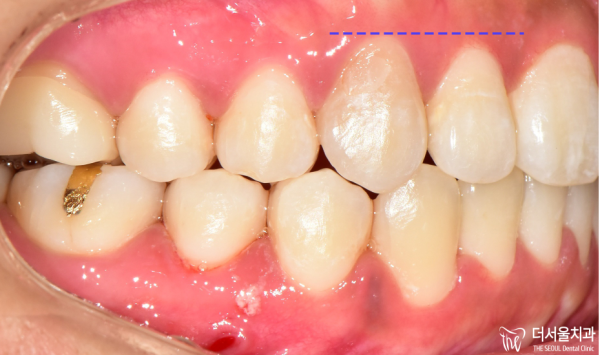

이 증례를 보시면 알 수 있는것 처럼

주변부위보다 월등하게 높은 위치에 송곳니가 나라고 있는것을

확인할 수 있습니다.

As you can see from this case,

The fangs are far higher than the surrounding area.

You can check it out.